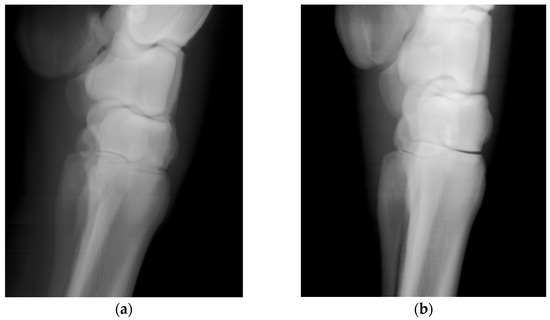

Scans of the horses’ distal forelimb, focusing on the hock and metatarsal, were performed utilizing the calibrated DH parameters. The images are clear and permit visualization of bone trabecular-level detail (Figure 5). For comparison, the second prismatic joint on the detector side’s θ parameter was returned to its initial value and an image of an equine lumbar segment phantom was collected (Figure 6). There is an obvious improvement in image sharpness with the calibrated system (Figure 6).

Figure 5. Lateral images of an equine carpus and metacarpus acquired in vivo from a standing horse, (a) acquired with 140 kVp and 12 mA source voltage and current technique and (b) acquired with a 70 kVp and 24 mA technique. For the 15 horses imaged, the beam was on for between 15 and 20 s.